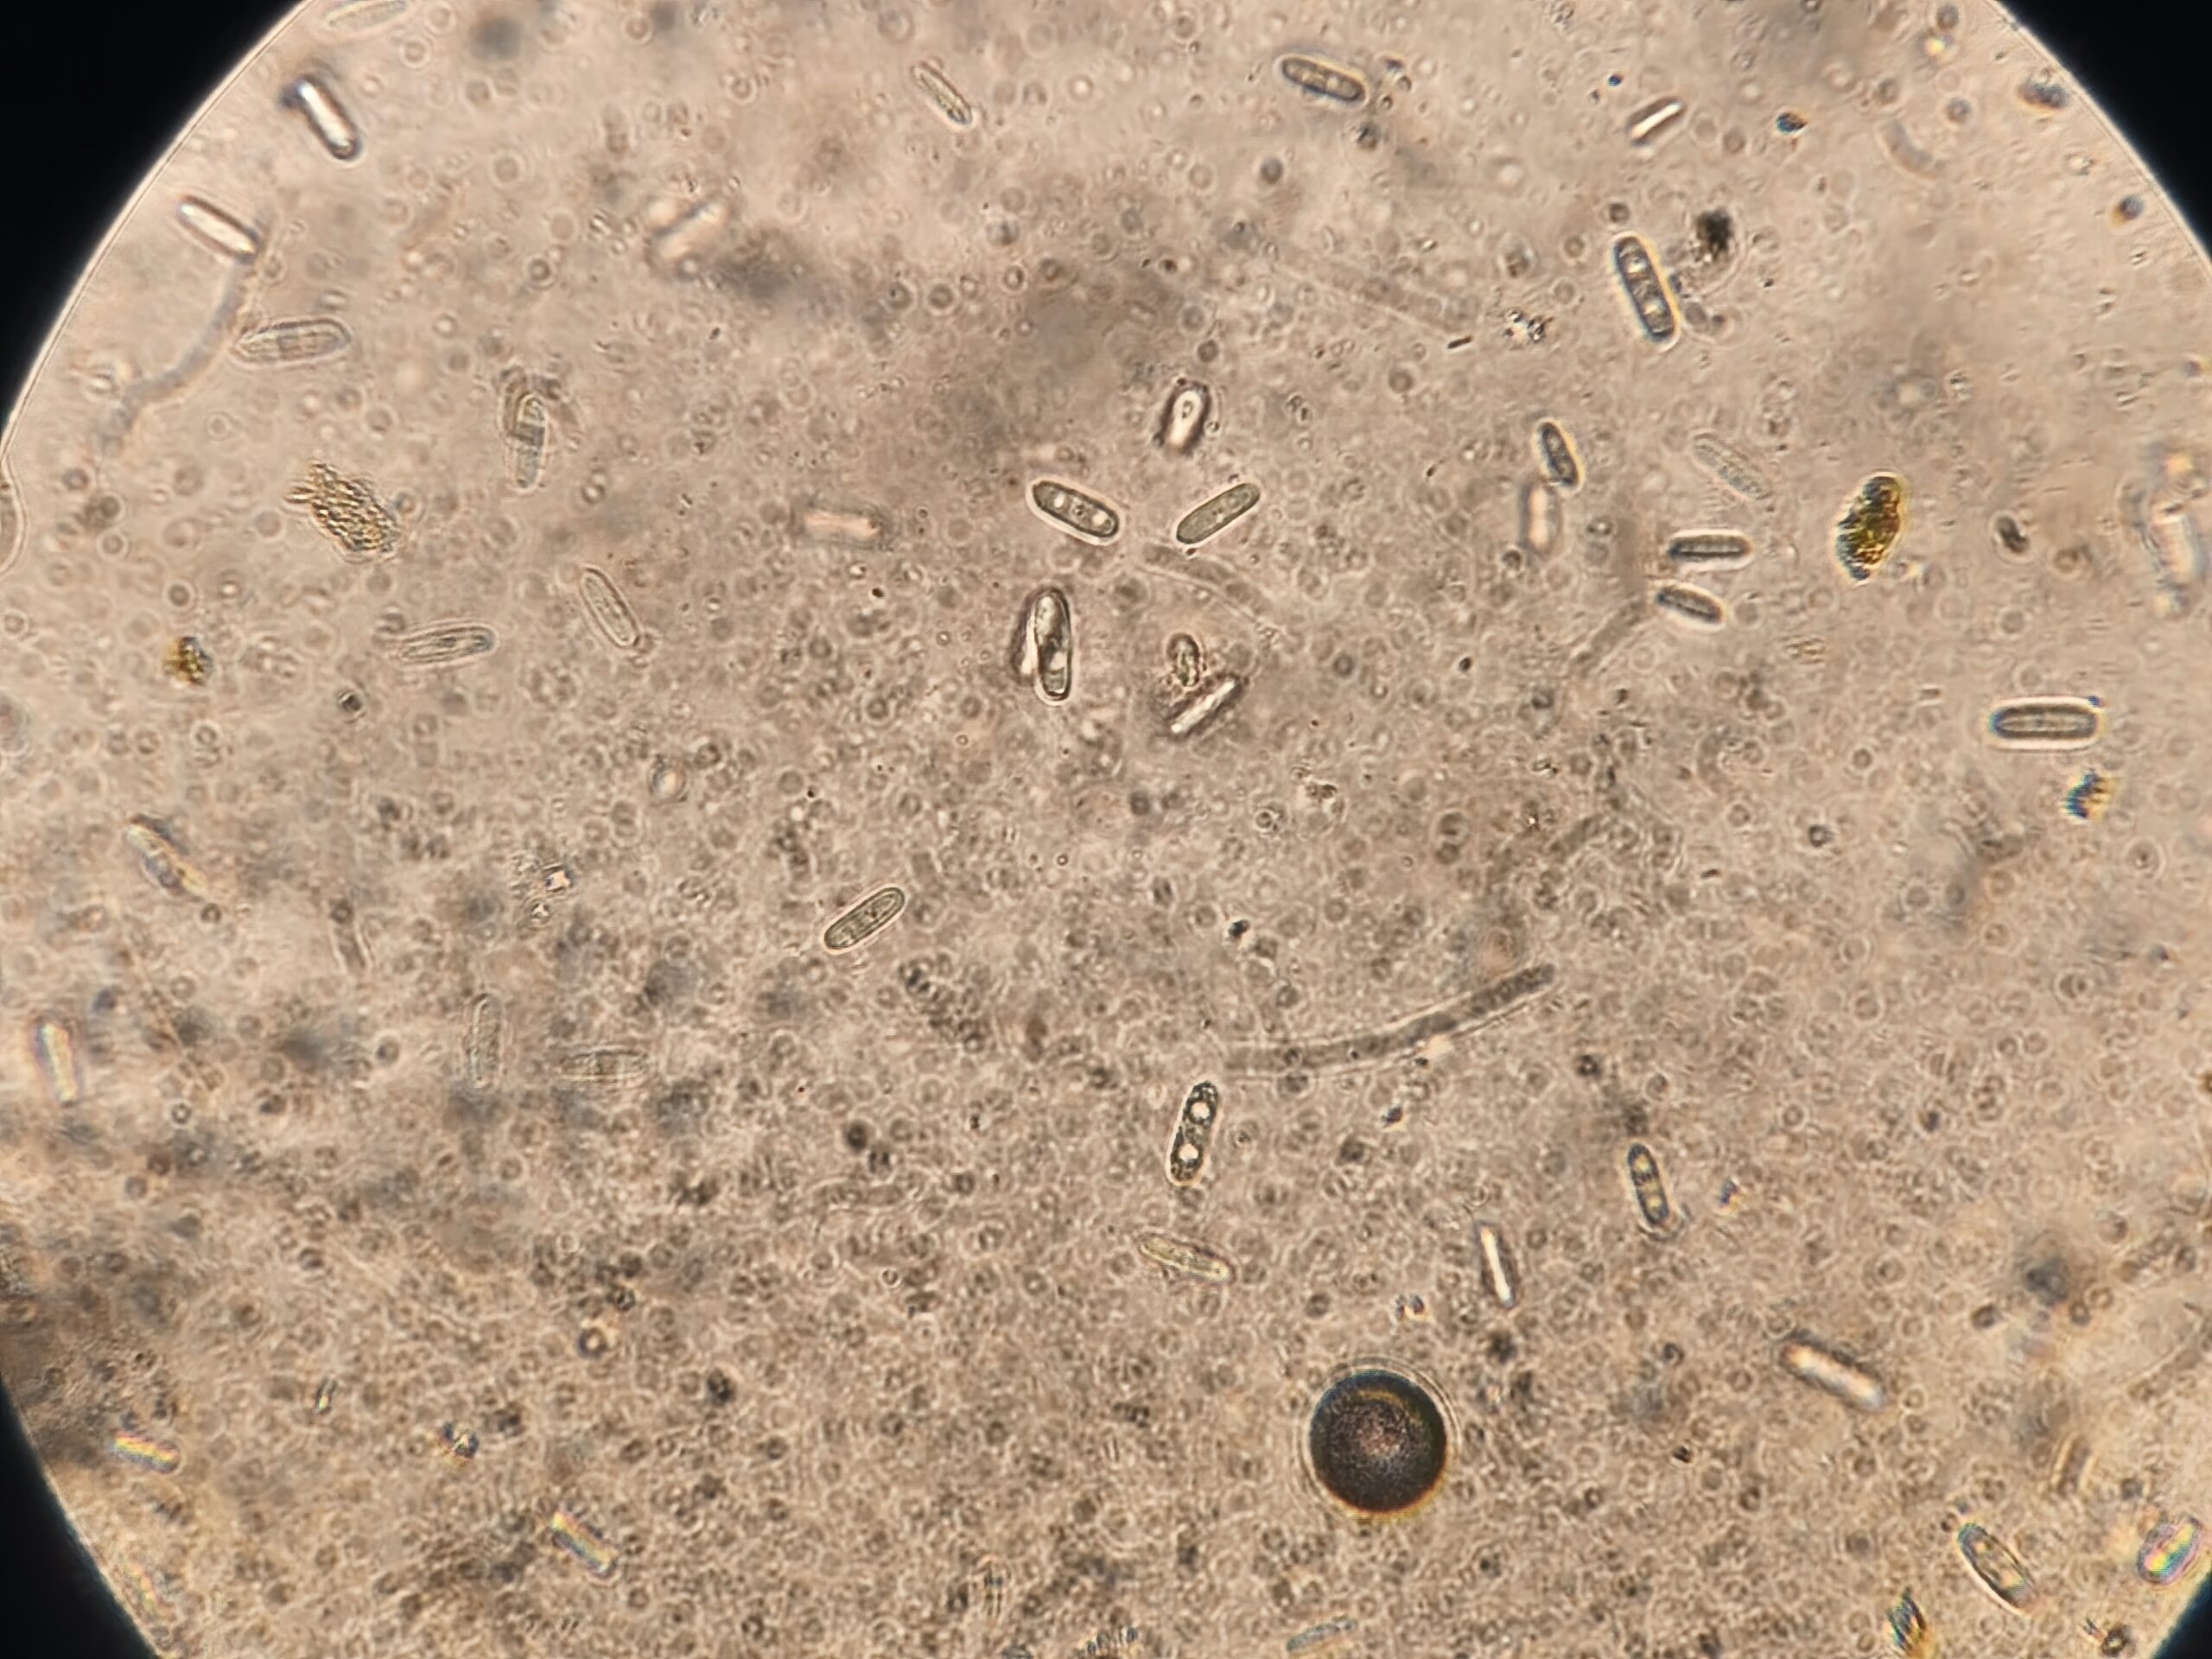

- examens coprologiques (selles) en microscopie

- examen cytologique